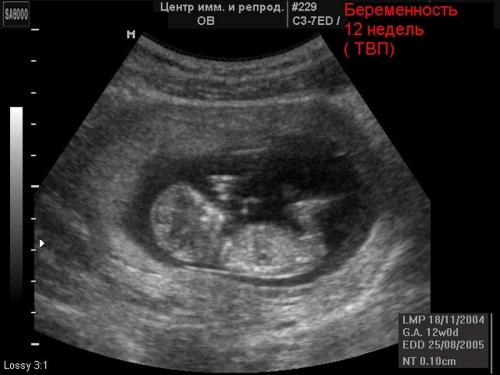

Если боли в животе имеют естественное происхождение, в некоторых случаях состояние женщины может ухудшится. Это может случиться после употребления женщиной крепких напитков (разные алкогольные напитки или кофе), поднятия тяжелых предметов, бессонницы, стрессовых ситуаций и др. По этой причине, если появились боли, лучше избегать подобных ситуаций и придерживаться рекомендаций врачей. - При беременности. Так как ребенок быстро растет, начинают растягиваться мышцы на животе, что становится причиной болей. В некоторых случаях эти боли являются достаточно сильными, вызывая очень неприятные ощущения и дискомфорт. Если самочувствие существенно ухудшилось, следует немедленно обратиться к врачу.